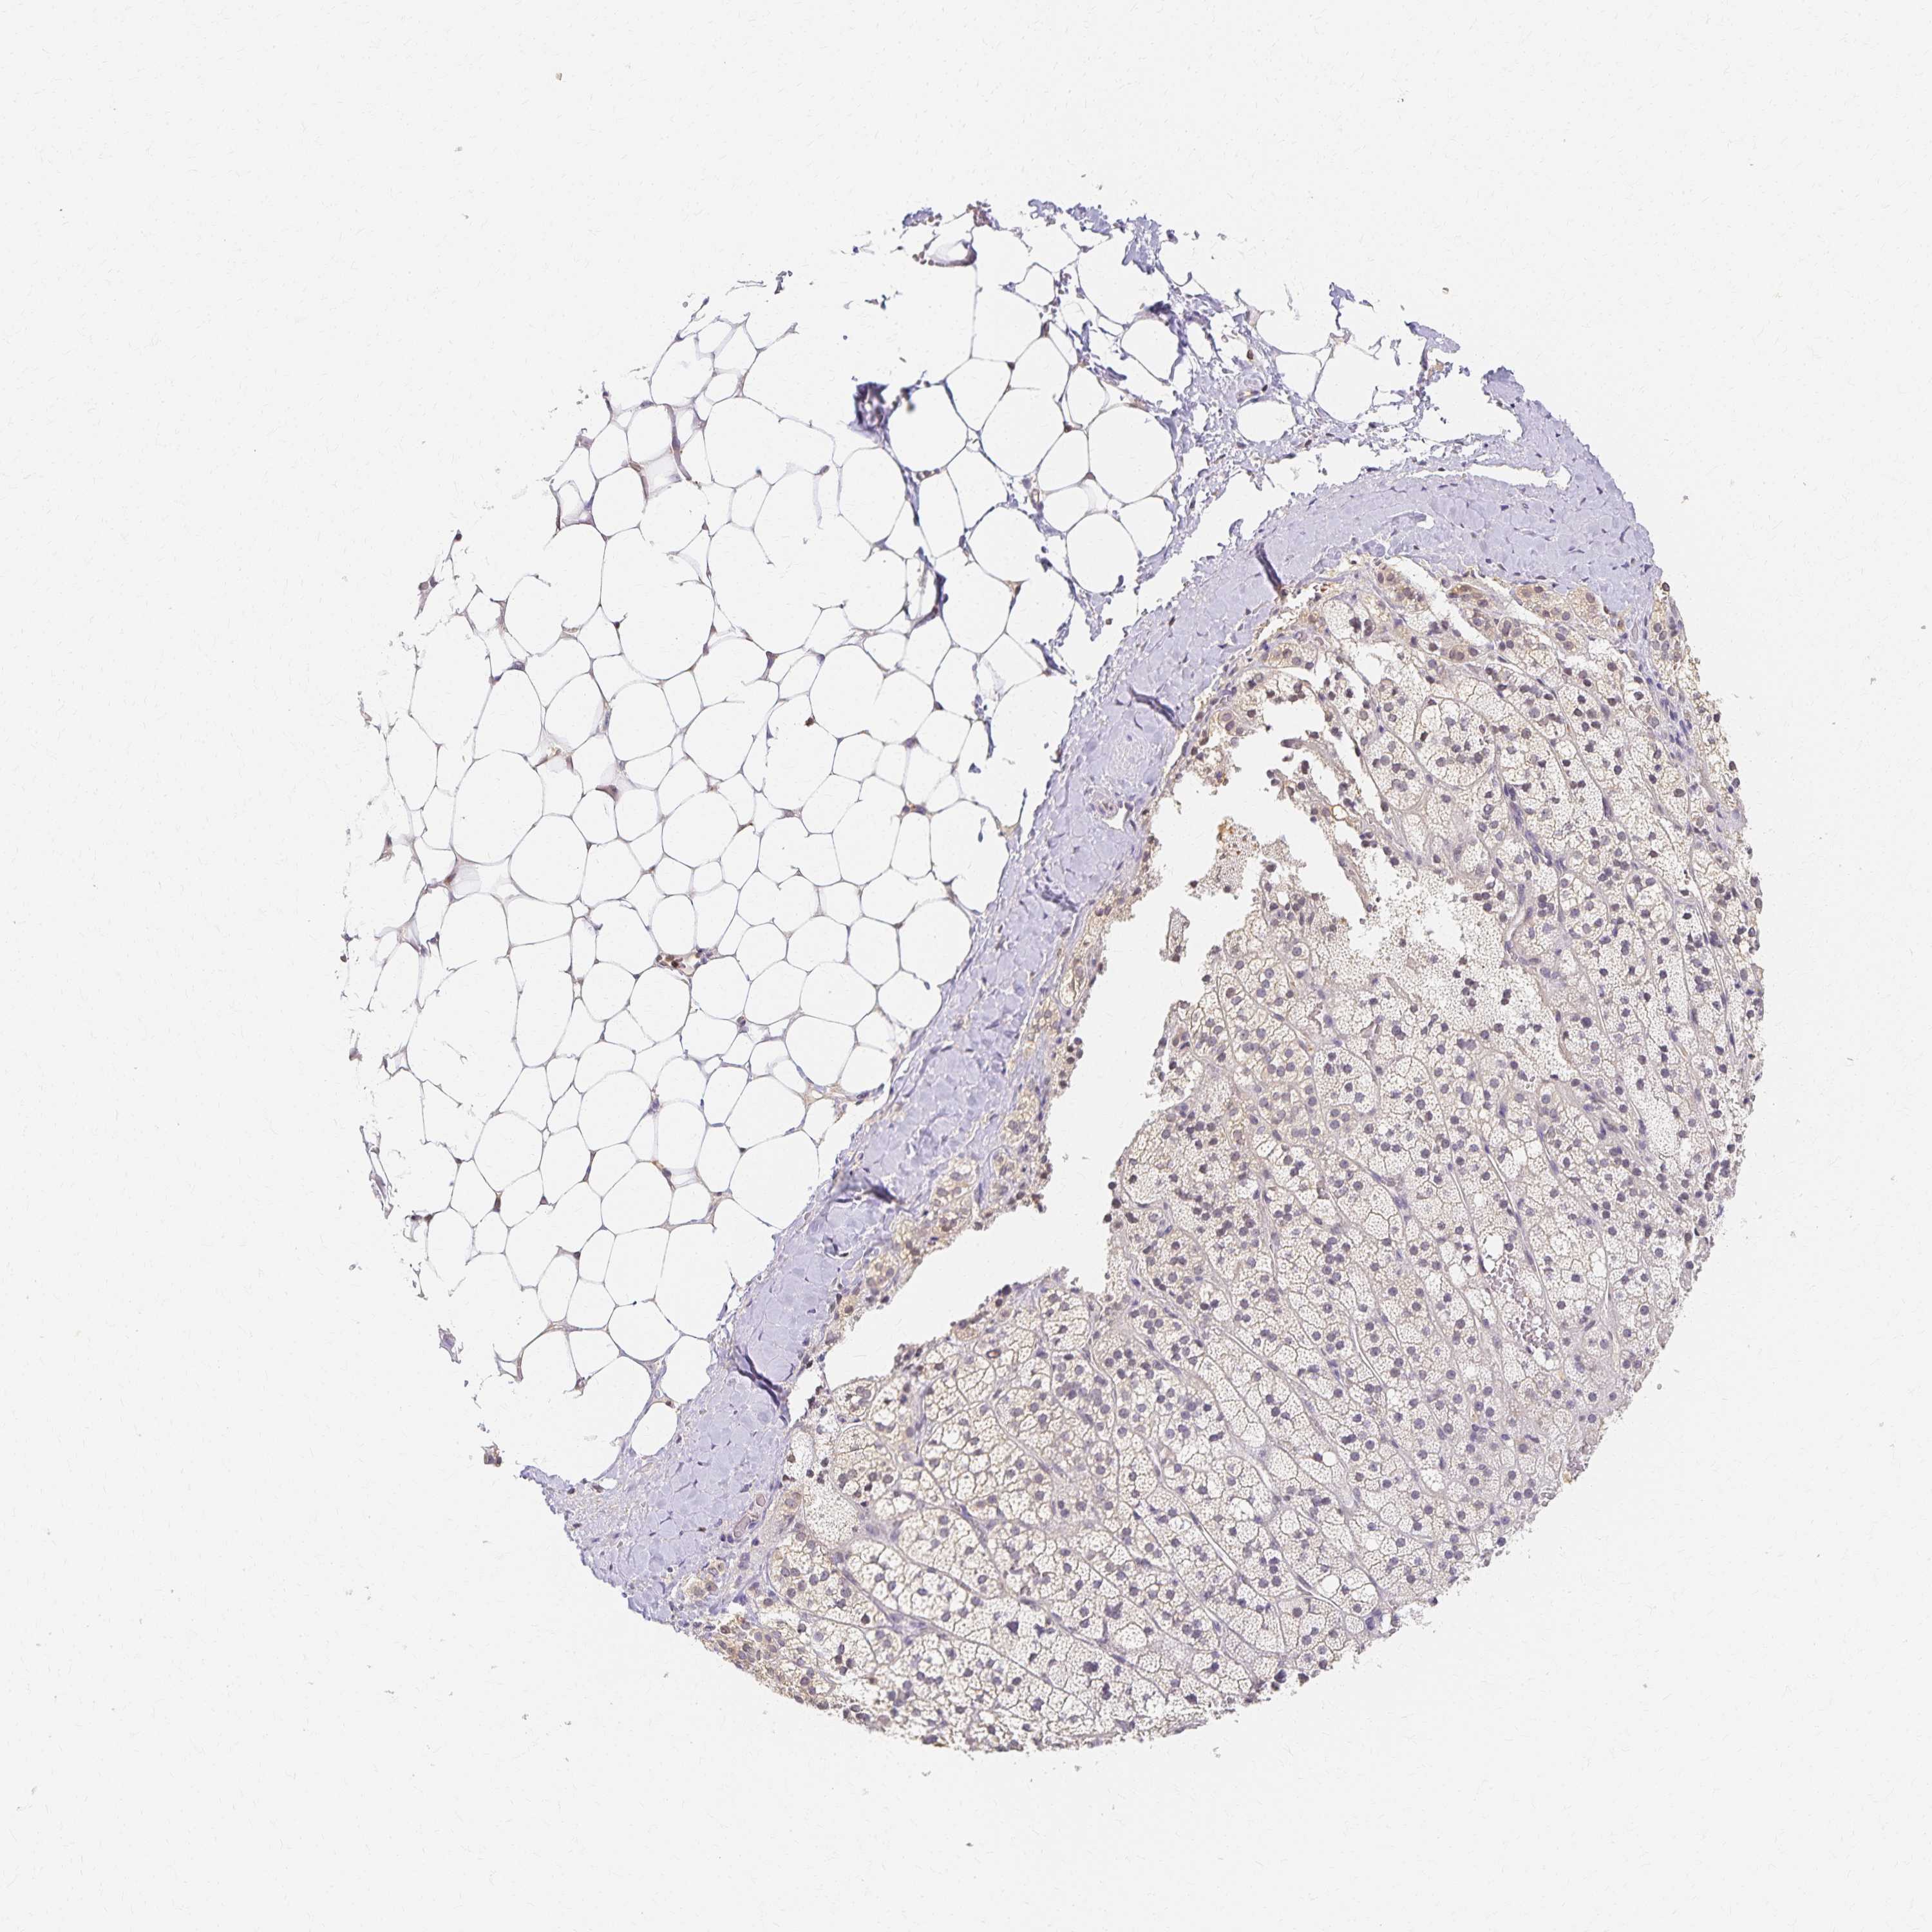

ADRENAL GLAND - Antibody stainingi

Antibody staining in the annotated cell types in the current human tissue is reported as not detected, low, medium, or high, based on conventional immunohistochemistry profiling in selected tissues. This score is based on the combination of the staining intensity and fraction of stained cells.

Each image is clickable and will lead to virtual microscopy that enables deeper exploration of all samples and also displays staining intensity scores, fraction scores and subcellular localization as well as patient and tissue information for each sample.

Antibody HPA012582Antibody CAB016087Antibody CAB032276

Glandular cells Not detectedNot detectedNot detected